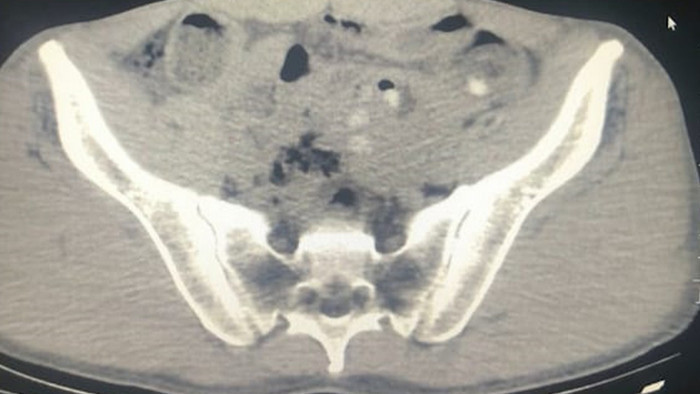

Gözaltına alınıp hastaneye götürülün şüphelilerin çekilen röntgenlerinde de midelerinde 45 kapsül metamfetamin tespit edildi.